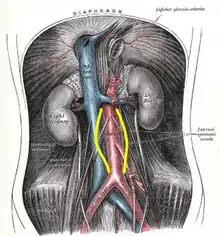

Hemodynamics affect the development of AAA, which has a predilection for the infrarenal aorta. The histological structure and mechanical characteristics of the infrarenal aorta differ from those of the thoracic aorta. The diameter decreases from the root to the aortic bifurcation, and the wall of the infrarenal aorta also contains a lesser proportion of elastin. The mechanical tension in the abdominal aortic wall is therefore higher than in the thoracic aortic wall. The elasticity and distensibility also decline with age, which can result in gradual dilatation of the segment. Higher intraluminal pressure in patients with arterial hypertension markedly contributes to the progression of the pathological process.[18] Suitable hemodynamic conditions may be linked to specific intraluminal thrombus (ILT) patterns along the aortic lumen, which in turn may affect AAA's development.[29]

An abdominal aortic aneurysm is usually diagnosed by physical exam, abdominal ultrasound, or CT scan. Plain abdominal radiographs may show the outline of an aneurysm when its walls are calcified. However, the outline will be visible by X-ray in less than half of all aneurysms. Ultrasonography is used to screen for aneurysms and to determine their size if present. Additionally, free peritoneal fluid can be detected. It is noninvasive and sensitive, but the presence of bowel gas or obesity may limit its usefulness. CT scan has nearly 100% sensitivity for an aneurysm and is also useful in preoperative planning, detailing the anatomy and possibility for endovascular repair. In the case of suspected rupture, it can also reliably detect retroperitoneal fluid. Alternative less often used methods for visualization of an aneurysm include MRI and angiography.